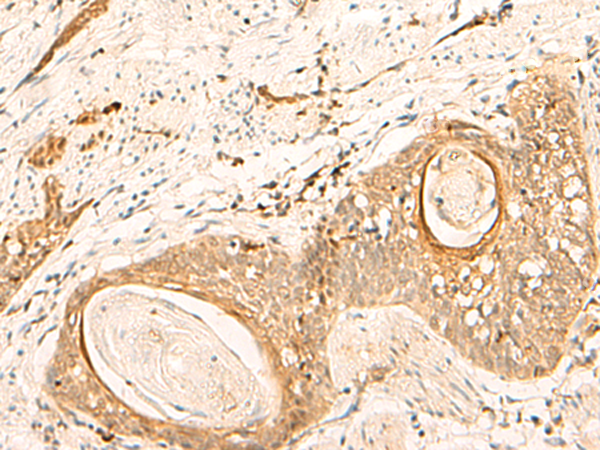

IHC positive control: |

Human tonsil and Human esophagus cancer |